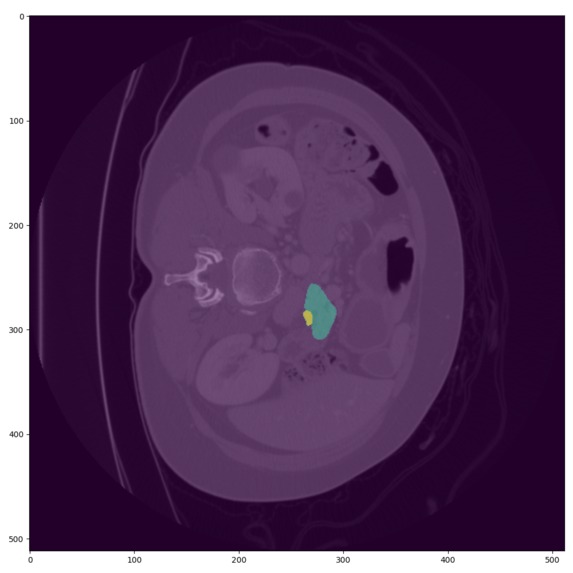

- ๐ผ๏ธ Advanced Imaging Analysis: Enhances diagnostic accuracy through integrated CT scan analysis using Nvidia MONAI [1].

- ๐ง AI Modeling: Optimized LightGBM models combined with Cohereโs RAG for interpretability, coupled with Nvidia MONAI.

- Conversion and processing of over 200K DICOM and NIfTI frames [2,3,4,5].